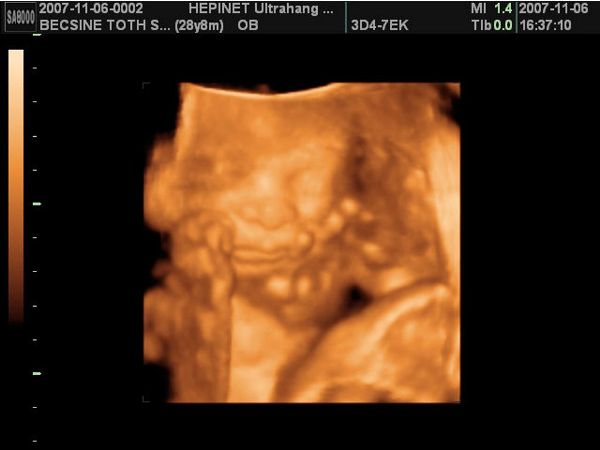

A második képen nyitva van a szeme is